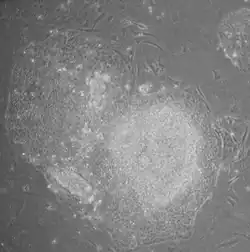

Human iPS cells colonies. The spindle-shaped cells in the background are mouse fibroblast cells. Only those cells comprising the center colony are human iPS cells.